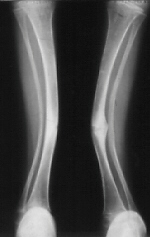

A 14-years-old boy. Body height 124 cm. Sillence type sporadic.

The first visit was at 2 years-old. He sustained one fracture in U/E and 8 fractures in L/E, underwent 10 operations, and has 60 degrees scoliosis. He became able to walk on crutches at 2 years old and had been a practical ambulator until 12 years old. He sustained a fracture at the distal end of right femur where an intramedullaly nail did not reached. He uses a wheelchair for long distant transportation. This case is supposed to be on the border line between ambulator and non-ambulator. The diameter of the femur was 10 mm at 3 years of age and 11mm at 13 years of age. No increase of diameter has been observed despite rather thin intramedullaly nailing.